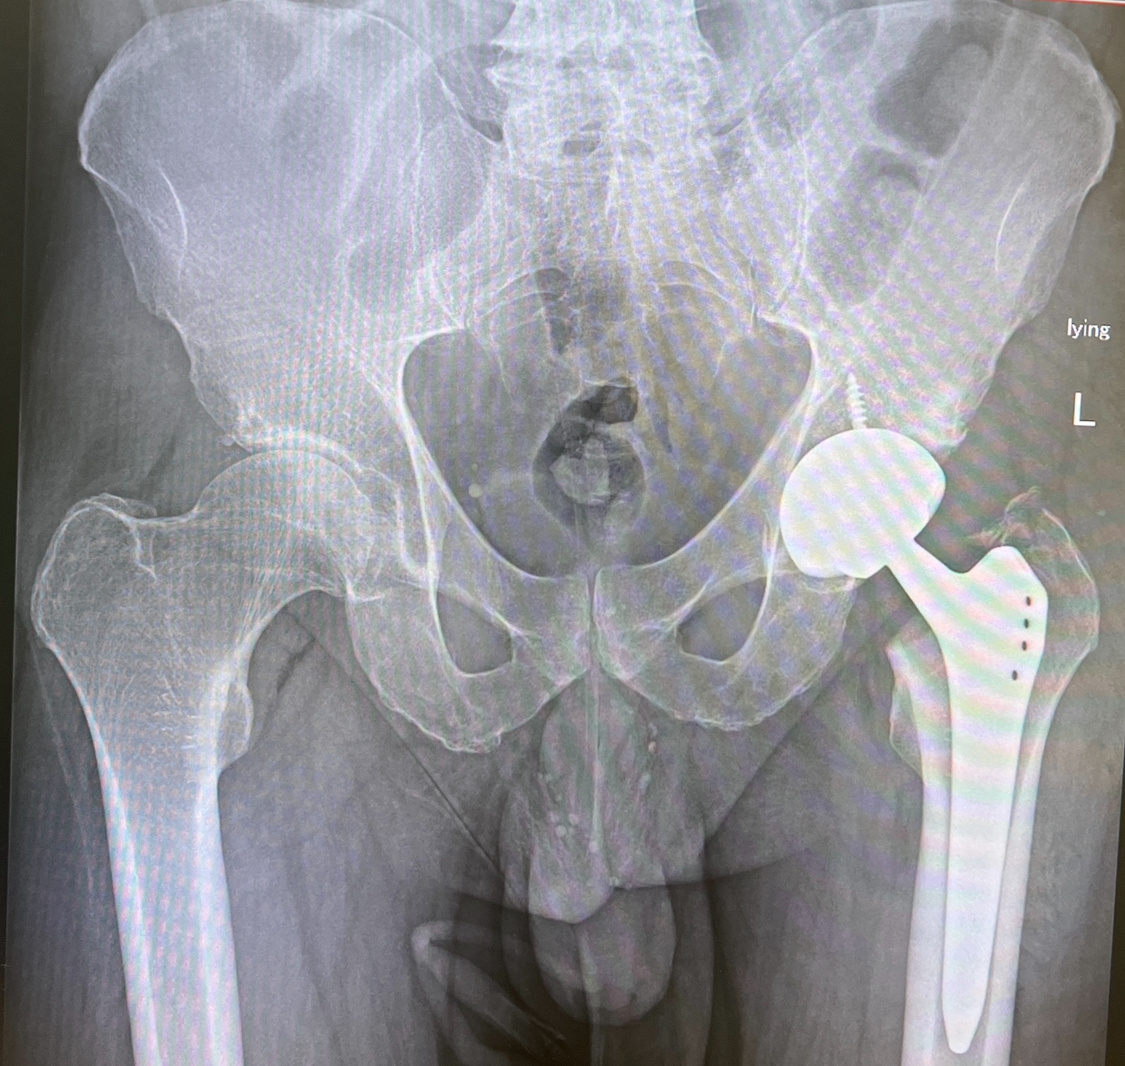

Итак, пациенту немного за 60. Очень спортивный. Несмотря на артродез голеностопного сустава, который я сделал лет пять назад, на отсутствующий мениск, гоняет на велосипеде по 100 км в день, играет в теннис, плавает и т.д.

Обычное эндопротезирование

Операция была в прошлый вторник. В среду начал ходить, в четверг прошёл весь наш коридор, в пятницу освоил ходьбу по лестнице, запросился на выписку - скучно, мало активностей ))). Еле уговорил остаться до субботы!